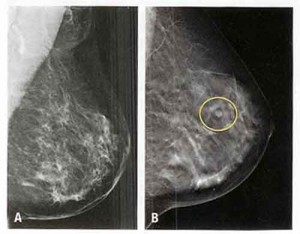

E’ necessario, ad esempio, rinnovare i criteri finora utilizzati per lo screening che dovra’ essere ‘su misura’: familiarita’ o condizioni genetico-ereditarie, mammella densa, terapia ormonale sostitutiva, precedenti condizioni patologiche del seno predisponenti al cancro e presenza di impianti protesici sono elementi da considerare per dividere le donne in tre categorie di rischio (normale, medio e alto). Le stesse condizioni potranno orientare per una diversa modulazione sia dello strumento diagnostico da utilizzare (mammografia, ecografia, risonanza magnetica) che per un diverso timing degli esami.

Quindi non piu’ la mammografia ogni 2 anni a tutte le donne ma una personalizzazione dei controlli sulla base del rischio individuale di ciascuna”. Secondo i risultati del progetto IMPATTO, promosso dall’Osservatorio Nazionale Screening, a partire dal 2007 tutte le regioni hanno attivato un programma di screening mammografico ma, attualmente, l’estensione effettiva e’ solo del 69,2%, con grandi differenze tra le aree geografiche. Inoltre, il tasso di partecipazione alla mammografia e’ in media del 55% (solo una donna su 2 accetta l’invito a sottoporsi all’esame), con un divario tra Centro-Nord e Sud dove i livelli di adesione sono al 40%.